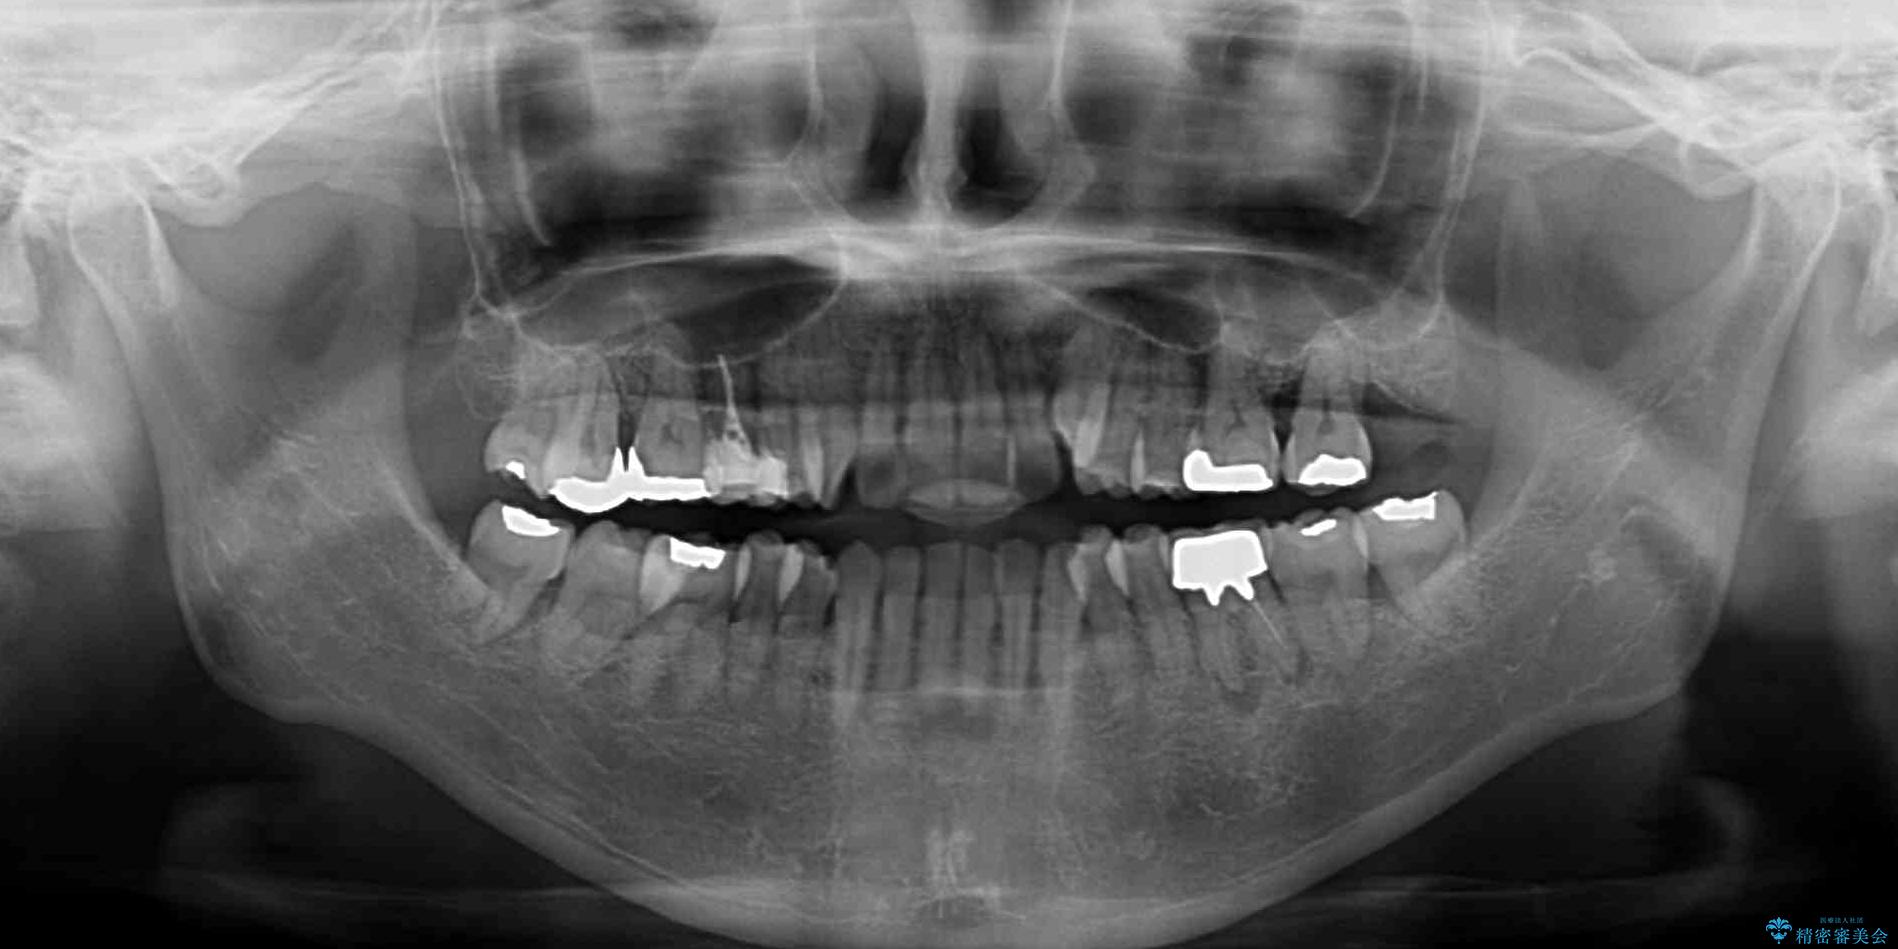

- 前歯のデコボコや八重歯を治したいとのことで来院された患者様です。

受け口傾向の骨格であり、前歯はクロスバイトまたは切端咬合となっており、下顎を中心に歯列全体の後方移動を行い、IPR(歯と歯の間を削る)によってデコボコが解消するように設計し、インビザラインにより治療を行うこととしました。

受け口傾向のインビザライン矯正は比較的治療を行いやすいため、きれいに仕上げることができました。舌の突出癖が顕著であったため、改善のためのトレーニングをしっかりと行っていただきました。